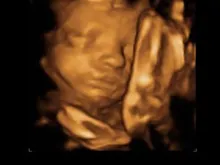

Suprema Corte respalda lei de Kentucky para que mães vejam ultrassom antes de um aborto

A Suprema Corte dos Estados Unidos rejeitou na segunda-feira, 9 de dezembro, um pedido de impugnação contra uma lei do... Leia mais